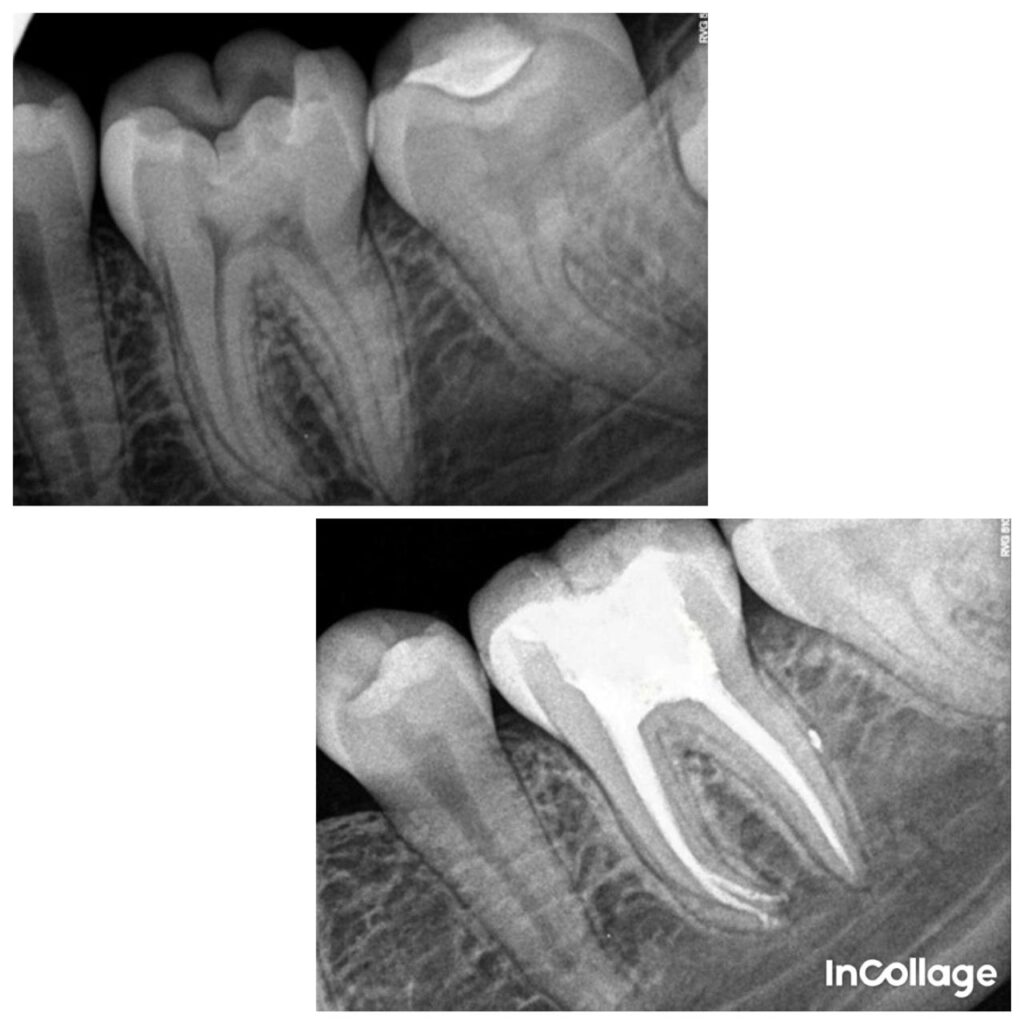

Single Setting Root Canal Treatement

- Magnification assisted Rotary Endodontics,

- Single Visit Root Canal Treatment (RCT)

- Retreatment of Failed Root Canal Cases

- Microscopic / Magnification-Assisted Endodontics